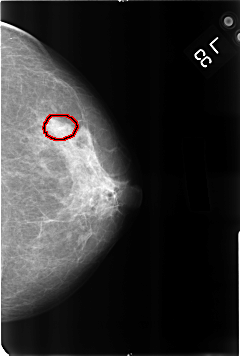

B_3215_1.LEFT_CC

FILE: B_3215_1.LEFT_CC.OVERLAY

TOTAL_ABNORMALITIES 1

ABNORMALITY 1

LESION_TYPE CALCIFICATION TYPE PUNCTATE DISTRIBUTION CLUSTERED

ASSESSMENT 2

SUBTLETY 3

PATHOLOGY BENIGN_WITHOUT_CALLBACK

TOTAL_OUTLINES 1

BOUNDARY